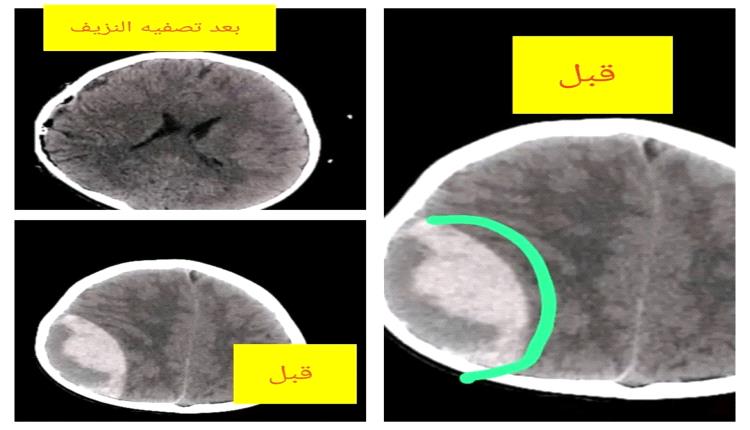

وكشفت نتائج الأشعة المقطعية (CT Scan) عن وجود نزيف دموي كبير فوق الجافية في الجهة اليسرى من الدماغ (Epidural Hematoma)، وهي من الحالات الخطيرة التي قد تؤدي إلى الوفاة في حال عدم التدخل الجراحي السريع.

وأمام خطورة الوضع، اتخذ استشاري جراحة المخ والأعصاب الدكتور عمر السروري القرار الفوري بإجراء عملية جراحية طارئة ودقيقة، تم خلالها فتح المنطقة المتضررة وتفريغ النزيف والسيطرة عليه وتنظيفها وفق المعايير الطبية المتبعة، بمشاركة فريق التخدير بقيادة الدكتور إبراهيم الأشول وطاقمه الفني، الذين كان لدورهم أثر بالغ في إنجاح العملية وإدارة الحالة طوال فترة الجراحة.